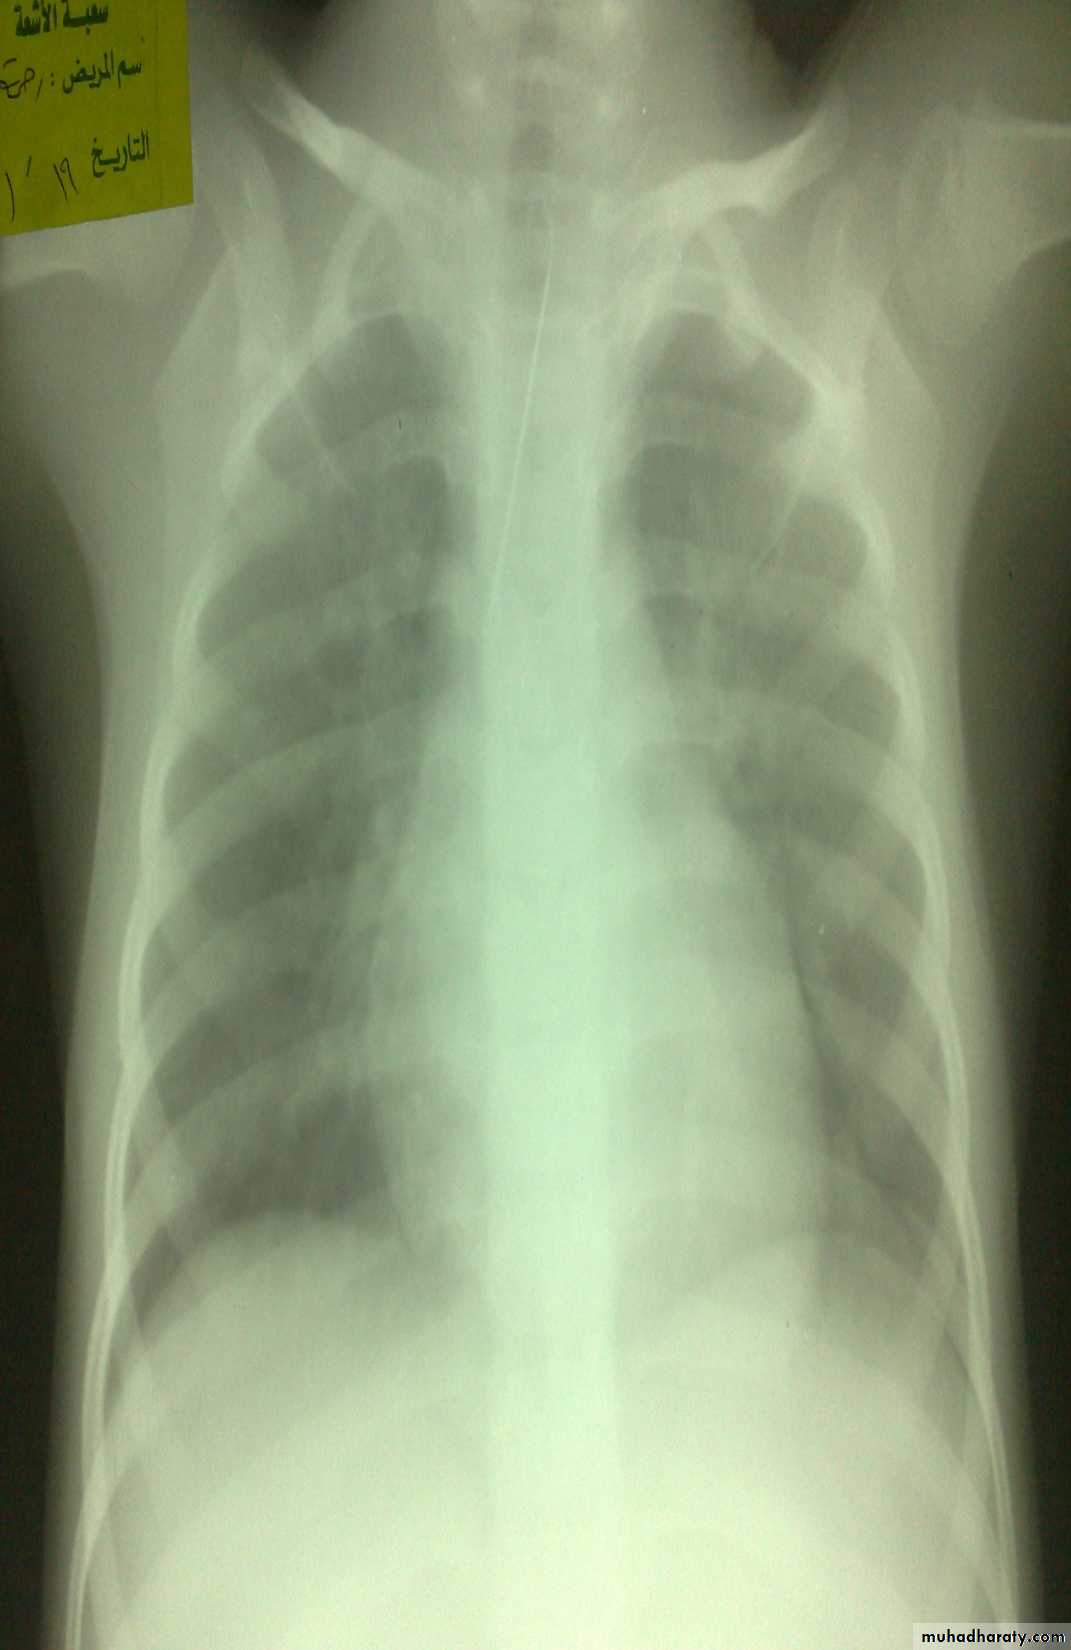

Vomiting in the First Months of Life

Diagnosis: pyloric stenosis(IHPS infantile hypertrophic pyloric stenosis—this name should be mentioned)

Presentation:

• Projectile vomiting (not present in first two weeks)• Olive mass in the abdomen

• Positive prestalsis(visible)

• FTT

Diagnosis:

• Clinically

• Ultrasound(width>14mm-length>16mm)

• Ba-meal dilated stomach – failure to pass to intestine – string sign

Treatment: in ER : resuscitation the pt(electrolyte+fluid)

surgery pyloromyotomy (rami stick surgery)Diagnosis: achalasia cardia